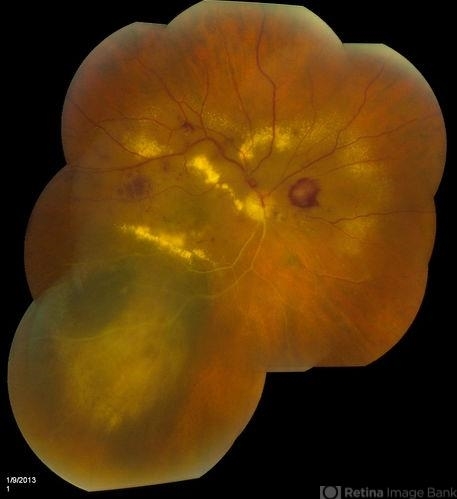

- radiation retinopathy

- Jason S. Calhoun, Department of Ophthalmology, Mayo Clinic Jacksonville, Florida

- Fundus camera

- Patient came with follow up on choroidal melanoma. Right eye that was treated back in June of 2009 with a radioactive implant. Vein occlusion is also present with VA - hand motion. Hemorrhages visible with hard exudates from the radiation retinopathy.